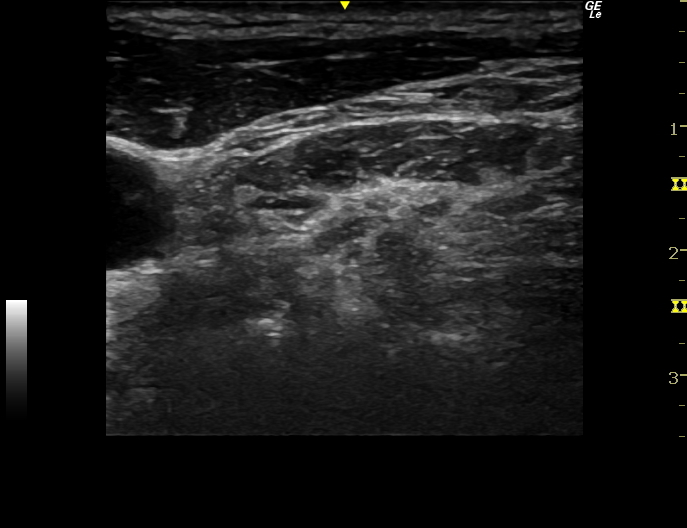

ファシアリリース・筋膜リリース・神経リリース

ファシアリリース・筋膜リリース・神経リリースは神経ブロックとは違いますが、エコーを使用して結合組織、筋膜、神経周辺に生理食塩水などを注入し、痛みやコリを治療するものです。エコーで見ると筋肉の筋膜以外にも、腱や靭帯、脂肪などにも白く厚く重なった癒着した組織が発生します。そこが痛みの原因となったり、組織間の滑走性が低下し可動性が制限されたり、血液の流れが悪くなっている可能性があります。

実際のファシアリリースの動画(再生ボタンを押してください)